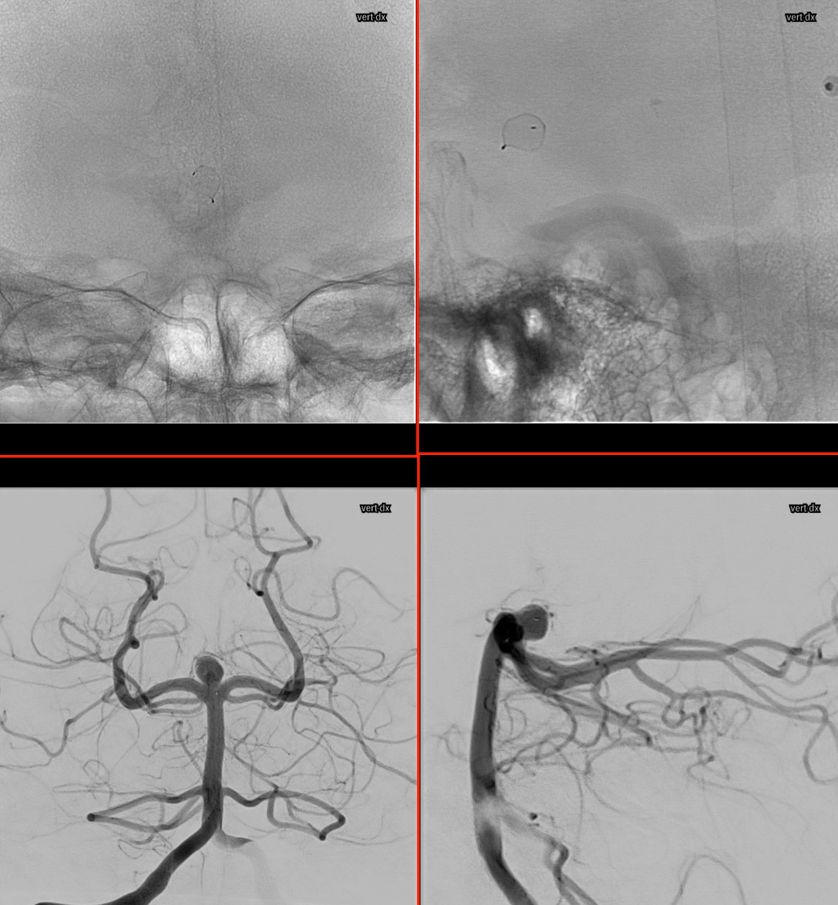

Basilar Bifurcation

Basilar tip aneurysm. A Percheron artery originating from right P1 is already evident.

3D (5 seconds) acquisition. In this case, all 3D and Vaso-CT acquisitions have been made with manual bilateral vertebral artery injection.

Below is Vaso-CT before Artisse. 22 cm FOV, 20 second acquisition. Bilateral pure contrast (300 mg/ml)Â manual injection with 20 ml syringes. Thin MIP reconstruction. No further reconstruction. The Percheron artery is well recognizable.

During Embo

Before detaching the Artisse. Same acquisition protocol as before Artisse positioning; bilateral 50% contrast (300 mg/ml) manual injection; followed by 50% FOV 5123 matrix. Note the artifacts caused by the radiopaque markers and pusher of the Artisse.